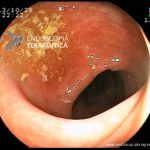

- Doença de Crohn em remissão – cicatriz